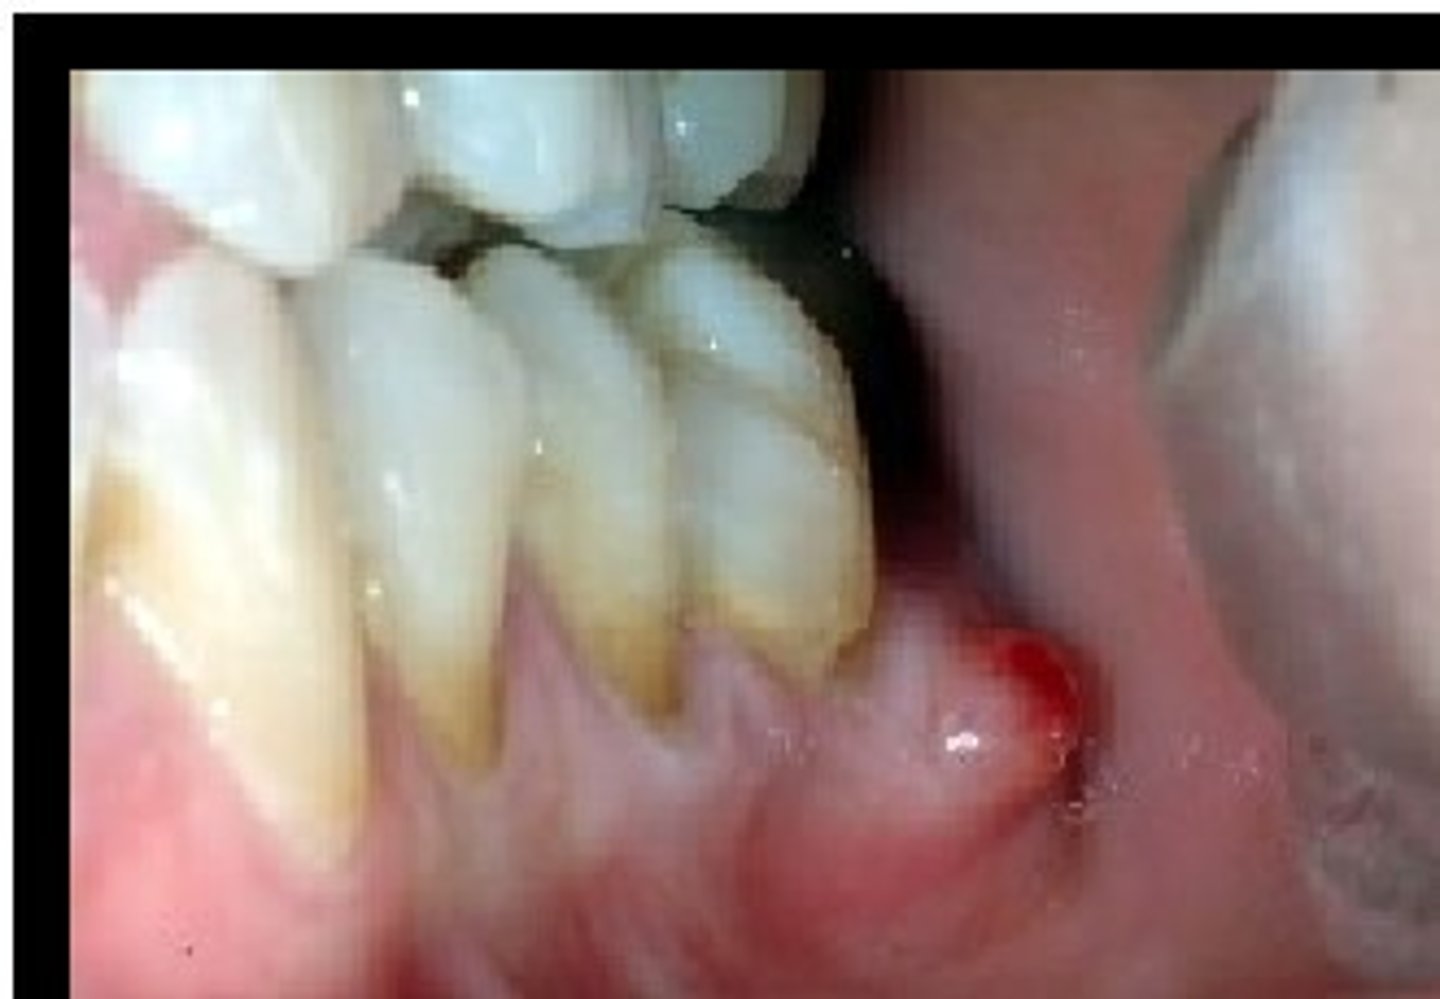

What is a parulis? (+ other names, common locations, associated with)

yellowish-red nodule on gingiva or palate

⢠associated with non-vital tooth

⢠AKA Cutaneous sinus, gumboil